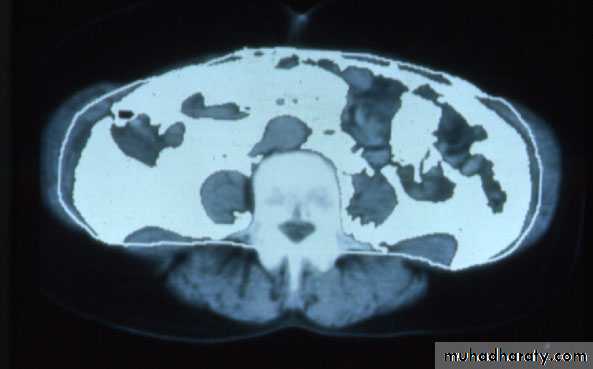

Normal

Visceral AdiposityCourtesy of Wilfred Y. Fujimoto, MD.

Visceral Fat DistributionIDF Waist Circumference